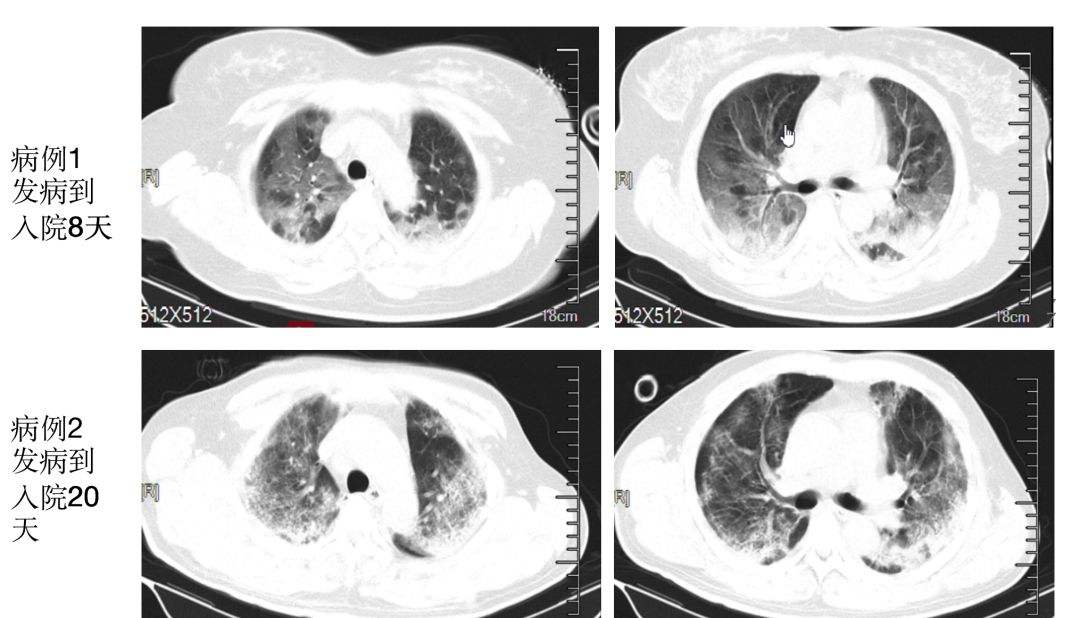

来源:华中科技大学同济医学院附属同济医院呼吸与危重症医学科

胸部影像学表现为早期呈现多发小斑片影及间质改变,以肺外带明显。进而发展为双肺多发磨玻璃影、浸润影,严重者可出现肺实变,胸腔积液少见。